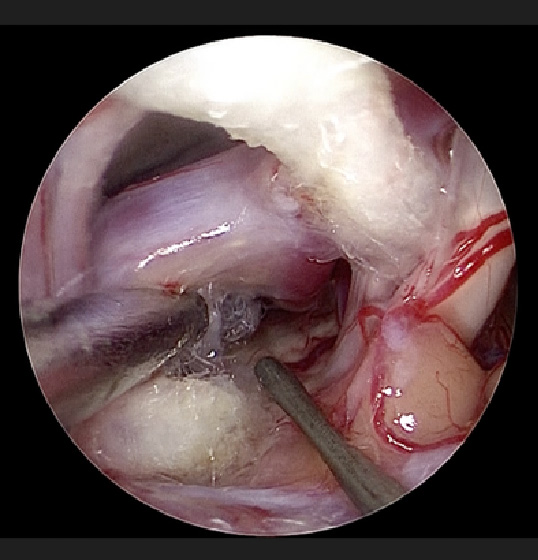

従来の顕微鏡

同部位に内視鏡を入れた手術中の映像

- ✔️同じ場所に内視鏡を入れ広角視野が得られ周囲の神経や血管、死角が見えるように!

- ✔️そのため創部もより小さく、安全な手術が可能に!